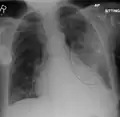

| A chest X-ray showing a very prominent wedge-shape bacterial pneumonia in the right lung | |

Normal AP CXR